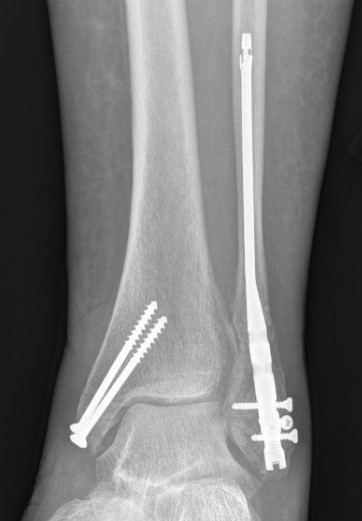

ORIF

Locking plates

Multiple syndesmotic screws